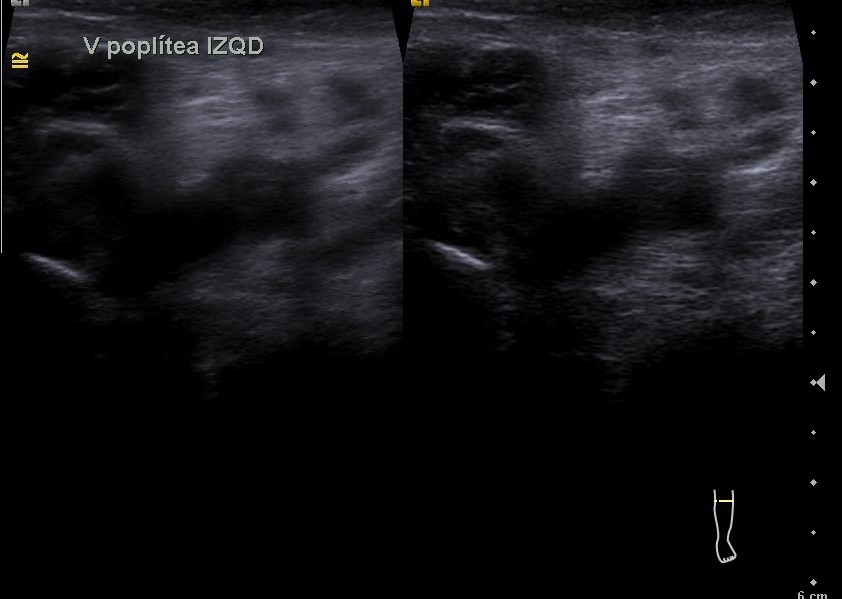

Hallazgos ecográficos

El estudio pone de manifiesto una ocupación trombótica aguda de la vena poplítea de pierna izquierda.

En el estudio se comparó la vena poplítea derecha, la cual a la presión ejercida con la sonda del ecógrafo sí comprimía, lo cual no sucedía con la vena poplítea izquierda.

Ambas venas femorales bilaterales eran permeables.